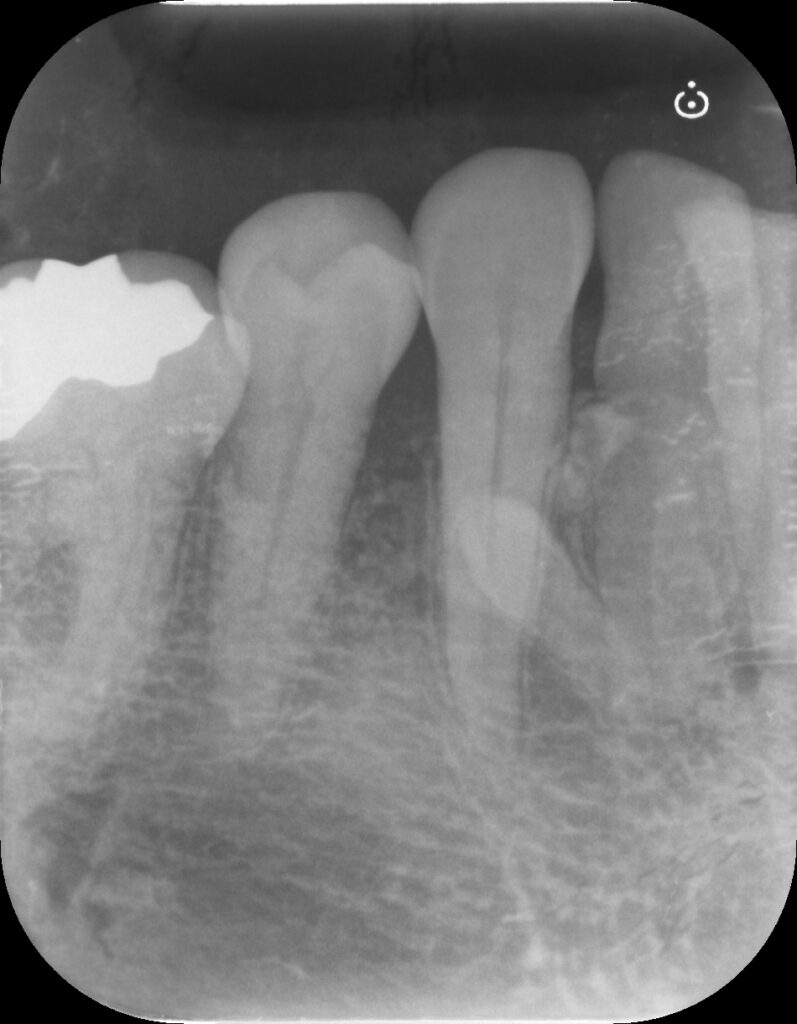

こんなときはレントゲンを撮るのが大切ですね。

レントゲンでは歯周病の所見も認めますが、レントゲンのみでは15mmもプローブが入るような写り方はしていません。

おそらく何か他にも原因があるのでしょう。(歯科関係者のみなさん過剰歯があるのは無視してください)

上のレントゲンからは少し骨が溶けている様子が見られます。